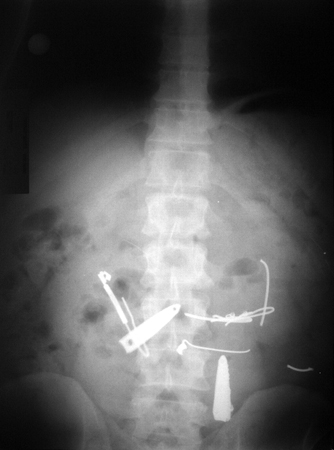

Radiografia abdominal simples revelando múltiplos corpos estranhos. Não há sinais de obstrução intestinal ou perfuração

De: Canda AE. BMJ Case Reports. 2009;2009:bcr12.2008.1354